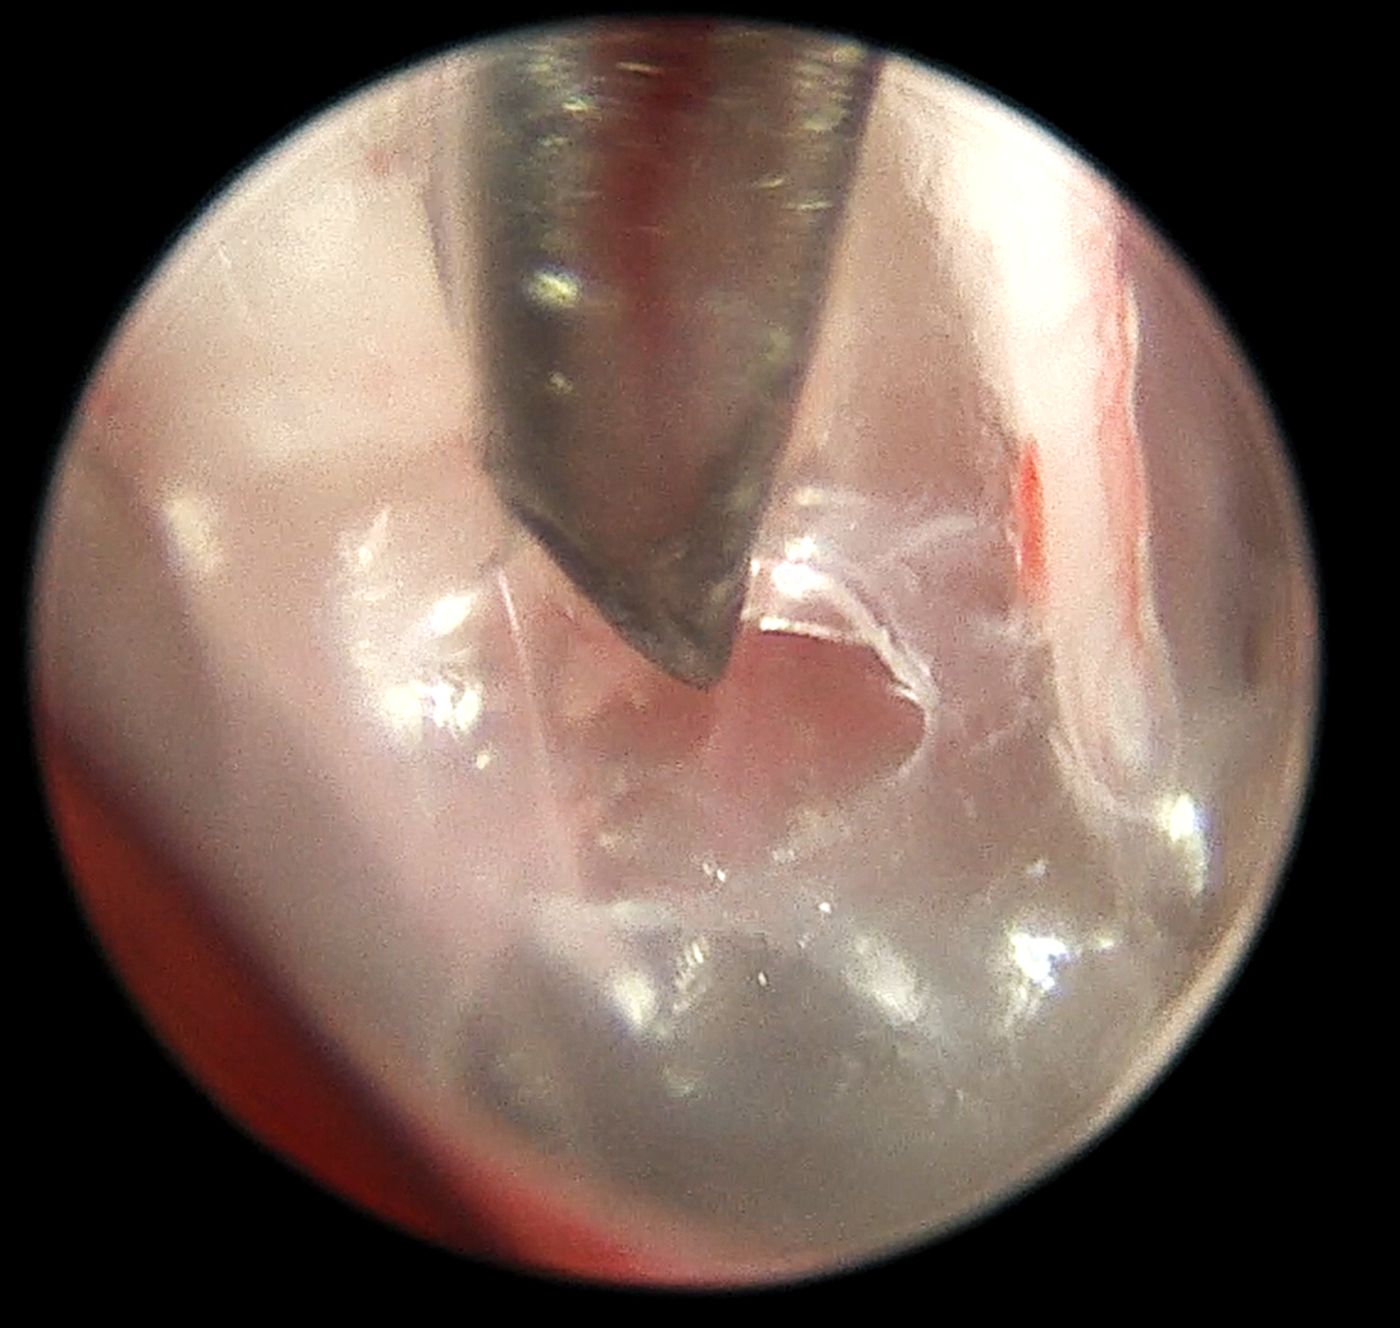

Diagnostyka endoskopowa zewnętrznych przewodów słuchowych (Otoendoskopia)

Głębokie płukanie przewodów słuchowych w znieczuleniu ogólnym

Myringotomia (nakłucie błony bębenkowej z oczyszczeniem z wydzieliny zapalnej) w celu diagnostyki i leczenia zapalenia ucha środkowego i wewnętrznego

Usuwanie ciał obcych (kłosy, bezoary)

Pobieranie biopsji tkanek zmienionych

Resekcję zmian nowotworowych w obrębie ucha zewnętrznego, także przy użyciu lasera